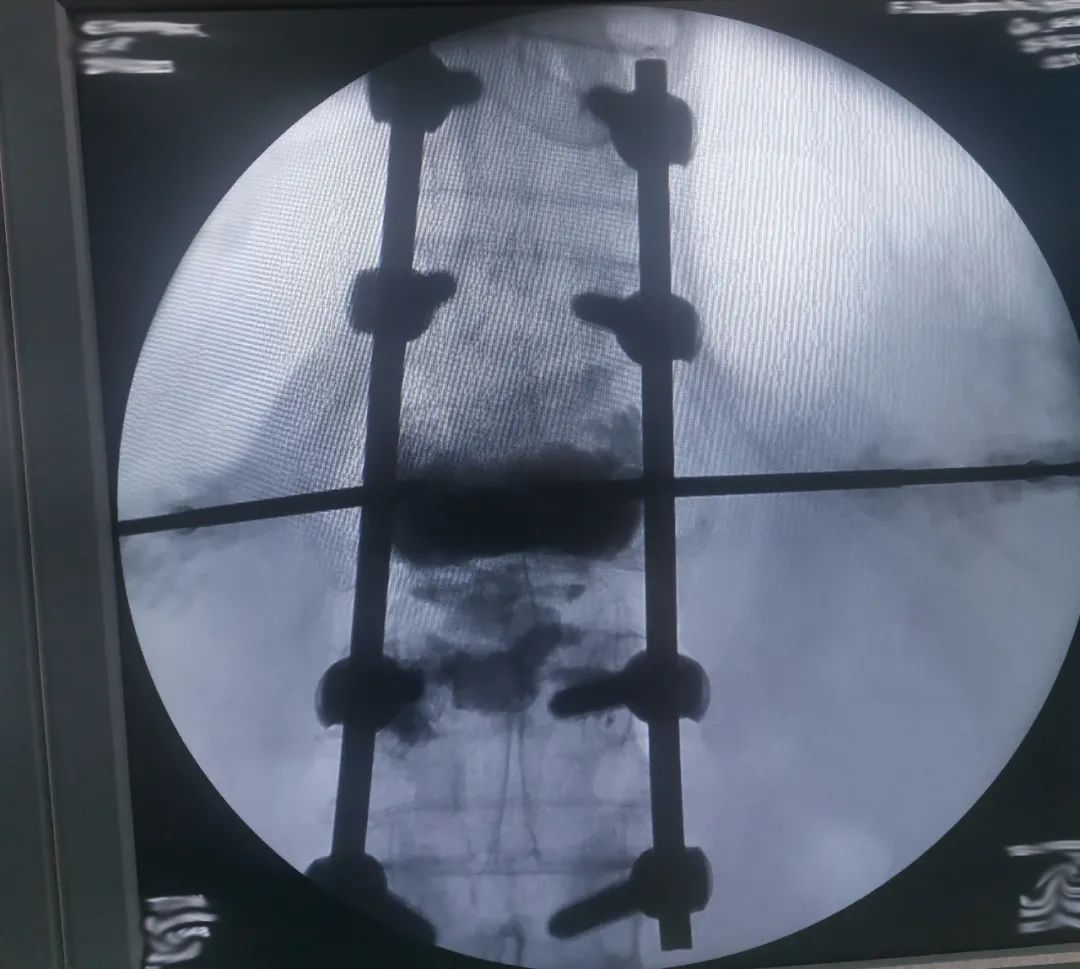

为了使张爷爷得到更舒适化的治疗,入院后,骨二科科室主任柯贤明主任医师与丁志敏副主任医师综合病史、查体及完善相关检查,组织手术团队进行详细讨论分析,在充分沟通并取得患者及家属同意后,骨二科手术团队在麻醉科的积极护航下,为患者行「全麻下胸腰椎骨折内固定+病椎椎体强化治疗」,手术过程十分顺利。